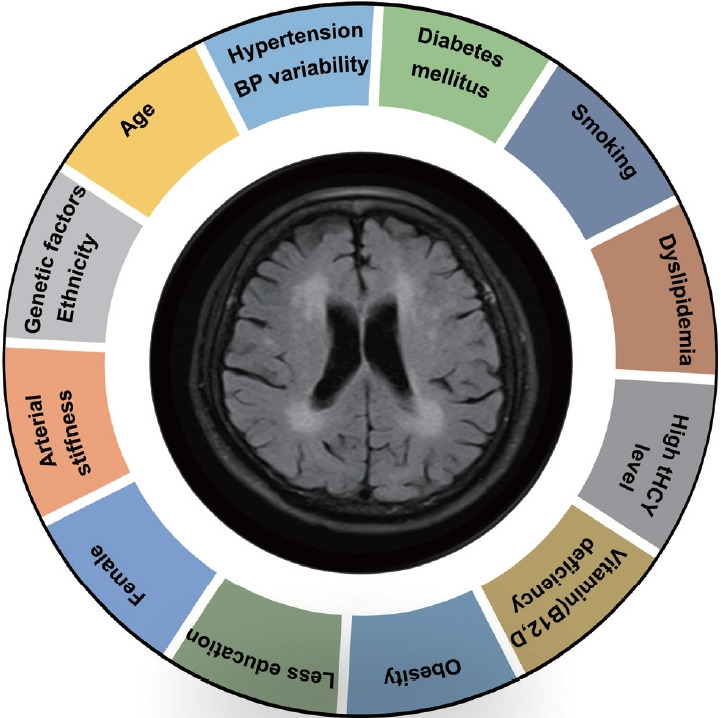

Leukoaraiosis (LA) manifests as cerebral white matter hyperintensities on T2-weighted magnetic resonance imaging scans and corresponds to white matter lesions or abnormalities in brain tissue. Clinically, it is generally detected in the early 40s and is highly prevalent globally in individuals aged >60 years. From the imaging perspective, LA can present as several heterogeneous forms, including punctate and patchy lesions in deep or subcortical white matter; lesions with periventricular caps, a pencil-thin lining, and smooth halo; as well as irregular lesions, which are not always benign. Given its potential of having deleterious effects on normal brain function and the resulting increase in public health burden, considerable effort has been focused on investigating the associations between various risk factors and LA risk, and developing its associated clinical interventions. However, study results have been inconsistent, most likely due to potential differences in study designs, neuroimaging methods, and sample sizes as well as the inherent neuroimaging heterogeneity and multi-factorial nature of LA. In this article, we provided an overview of LA and summarized the current knowledge regarding its epidemiology, neuroimaging classification, pathological characteristics, risk factors, and potential intervention strategies.